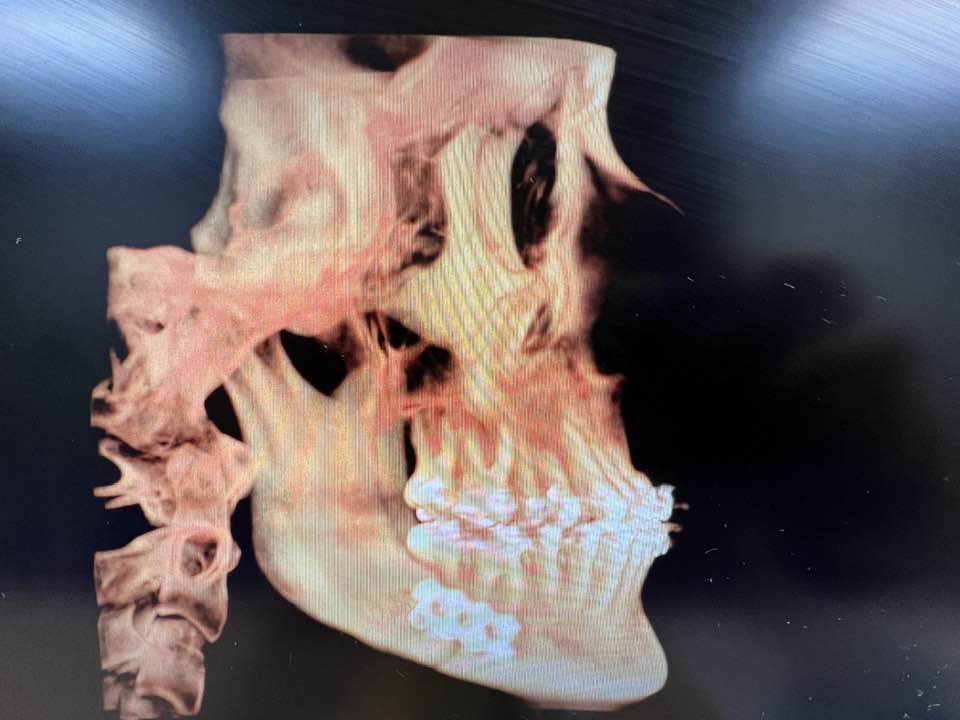

TMJ Surgery: Temporomandibular Joint Disorders (TMD) can significantly impact a patient’s quality of life, causing pain, discomfort, and restricted jaw movement. The experienced surgeons at Oral Surgery & Implant Specialists offer advanced surgical interventions to address TMD, providing relief and restoring optimal jaw function for their patients.

Cleft Lip and Palate Repair: Cleft lip and palate are among the most common birth defects, requiring specialized surgical care to restore normal facial structure and function. The skilled surgeons at Oral Surgery & Implant Specialists have extensive expertise in performing cleft lip and palate repair surgeries, helping children achieve optimal oral health and confidence in their appearance.

Facial Cosmetic Surgery: In addition to their expertise in oral and maxillofacial surgery, the team at Oral Surgery & Implant Specialists offers elective facial cosmetic procedures to enhance patients’ facial aesthetics. From chin augmentation to eyelid surgeries, these procedures are performed with precision and artistry to achieve natural-looking results and boost patients’ self-confidence.